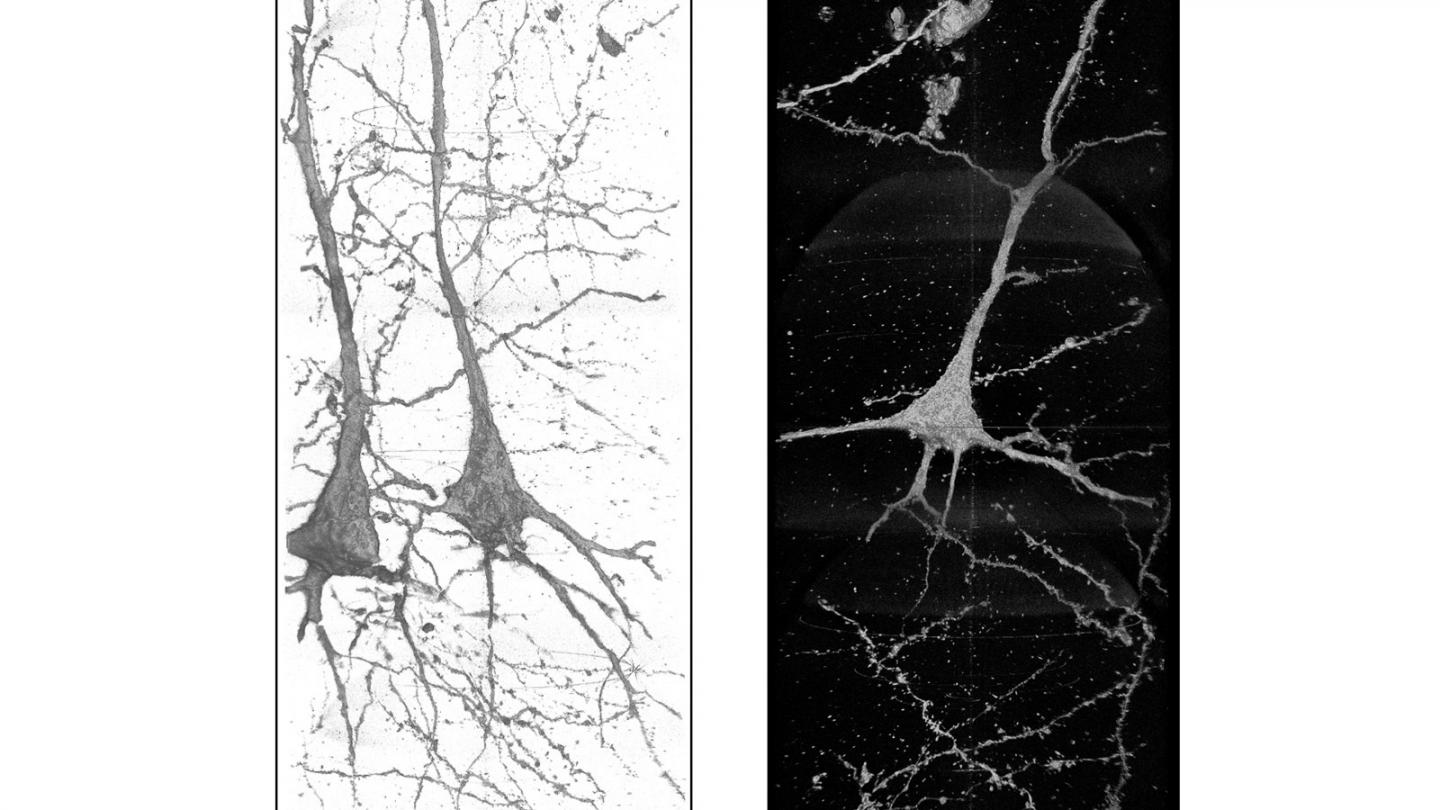

image: These 3D images of neurons in the brain of a schizophrenia patient show wavy, distorted neurites, which indicate that the condition may be linked to the shape of the neurons. X-ray images were taken at the Advanced Photon Source.

What these images showed is that the structures of these neurons are uniquely different in each schizophrenia patient, which Mizutani said is evidence that the disease is associated with those structures. Images of healthy neurons were relatively similar, while neurons from schizophrenia patients showed far more deviation, both from the healthy brains and from each other.